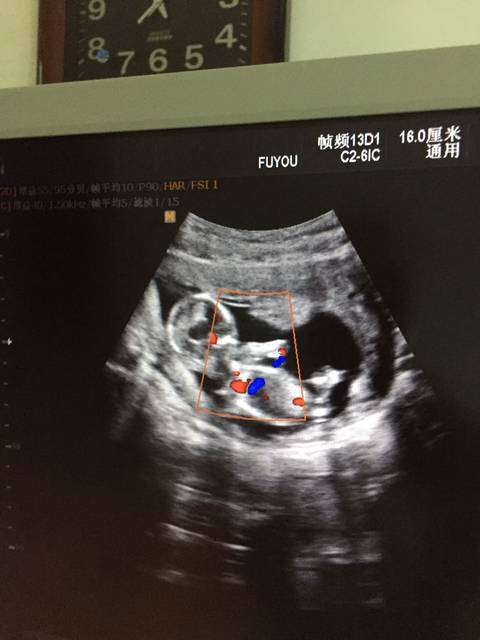

怀男孩nt报告图片

nt单子有人会看nub男女吗?

nt彩超是什么检查图片_纵览新闻